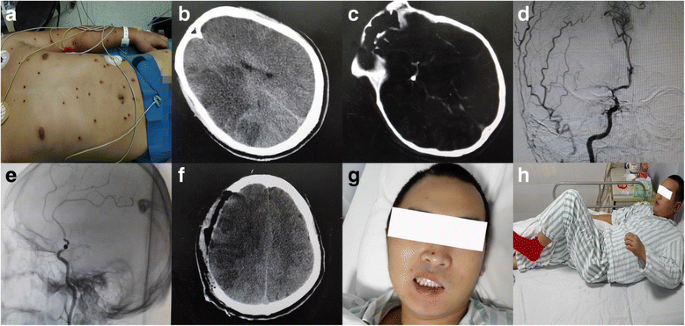

A 24-year-old man suffered from an accidental gunshot injury on December 15, 2015 (Fig. 1a). An emergency CT scan showed pellets in the saddle area of the brain (Fig. 1c), pericardium, stomach and intestines. On evaluation, he was in stable condition with a normal sinus rhythm on electrocardiography and normal blood pressure. Symptoms such as nausea, vomiting, dizziness, dystaxia, hyperspasmia and reduction in myodynamia were not found. The patient received fluid infusion, dehydration, analgesia and some other therapies to relieve his symptoms.

Picture and CT image of the patient. The patient with gunshot wounds showed recovery of the intracranial blood supply and physical ability gradually due to our contribution of surgery.a Multiple gunshot wounds in the skin of this patient; b CT scan revealing large parts of low-density shadows in the right frontal lobe, right parietal lobe and right temporal lobe before the surgery; c CT scan revealing the pellet lodged in the brain; d, e DSA showed the branches after the initial part of the right middle cerebral artery (MCA) were obliterated; f CT scan showed decreased low-density areas with the midline moving back 24 h after the surgery; g Posterior-anterior picture of the patient 2 weeks after the surgery showed a decreased difference between two sides of the face; h The patient left the hospital with myodynamia degree III of his left upper limb, degree V of the proximal part of his left lower limb and degree V of the distal part of his left lower limb

Cranial CTA and digital subtraction angiography (DSA) was performed immediately and it showed a high-density shadow in the initial part of the right middle cerebral artery (Fig. 1d, e). The branches after the initial part were obliterated. The right anterior and right posterior cerebral artery compensated for the blood supply of the right middle cerebral artery. However, a CT scan showed large areas of low-density shadows in the right parietal lobe and right temporal lobe with midline shifting to the left side 2 days later. Physical examination of the nervous system showed a myodynamia degree 0 of his left upper limb, degree I of the proximal part of his left lower limb and degree II of the distal part of his left lower limb. The patient presented with somnolence and dysphoria. He could still speak logically. His pupils were 3 mm in diameter and were of equal size with sensitive responses to light reflexes. The patient’s symptoms gradually became more serious. The patient could not talk logically and appeared irritable in the afternoon.

Although the formation of compensatory circulation had taken place, the ischemic situation of the patient’s brain tissue had not improved effectively according to the low-density areas in the CT scan examination (Fig. 1b). The patient was diagnosed as having an acute cerebral infarction. Acute cerebral infarction is a contradiction for cranial artery by-pass operations. It has been reported that DC surgery can lower intracranial pressure but there is little evidence to show that this surgery can help improve the blood supply.

In terms of the dangerous and urgent situation of this patient, he was taken into the operating room. A DC and dura turning-over surgery was conducted to help him from becoming worse under general anesthesia. We removed a part of the skull in the area of the frontal bone, temporal bone and parietal bone (Fig. 2a). We made an incision in his dura mater to release the intracranial hypertension and covered his brain tissue with turning-over of his dura mater onto the brain with the outside surface (Fig. 2b, c). Afterwards, the patient’s brain artery beat rhythmically again. The incision was closed with a relaxation suture. Treatments after the surgery included hemostasis, antibiotics, analgesia, diuretics and neurotrophic drugs. CT scan showed decreased low-density areas with the midline-line moving back 24h after the surgery (Fig. 1f).

Five days after the surgery, the patient started to speak logically but was still in lethargy. Medical examination of the nervous system showed myodynamia degree I of his left upper limb, degree II of the proximal part of his left lower limb and degree II of the distal part of his left lower limb. Nine days after the surgery, the myodynamia degree of his left upper limb rose to degree II. Twelve days after the surgery, the patient turned became conscious without somnolence. Posterior-anterior picture of the patient 2 weeks after the surgery showed a decreased difference between two sides of the face (Fig. 1g). Fifteen days after the surgery, the myodynamia degree of his left lower limb rose to degree IV. Eighteen days after the surgery, medical examination of the nervous system showed myodynamia degree IV of his left upper limb, degree V of the proximal part of his left lower limb and degree V of the distal part of his left lower limb (Fig. 1h). We advised him to take more exercise to help functional recovery of his muscle and ankles. Twenty-three days after the surgery, the patient was conscious and spoke logically. Cranioplasty surgery was performed successfully 3 months later.